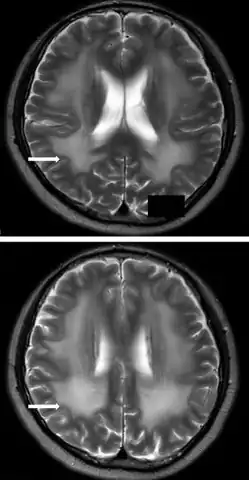

Brain MRI

Abnormal white matter signals in Brain MRI is a near-universal sign in patients with LAMA2-MD. These white matter abnormalities appear as hyperintense signals on T2-weighted and FLAIR brain MRI images especially in locations that are originally myelinated in the immature brain as the periventricular area. Occasional MRI abnormalities include cortical malformations as polymicrogyria, lissencephaly, pachygyria.[1][2][15][5] In LAMA2-MD there seems to be a directly proportional relationship between the magnitude of white mater and cortical abnormalities on brain MRI and the degree of motor dysfunction in terms of the ability to sit and walk.[15]